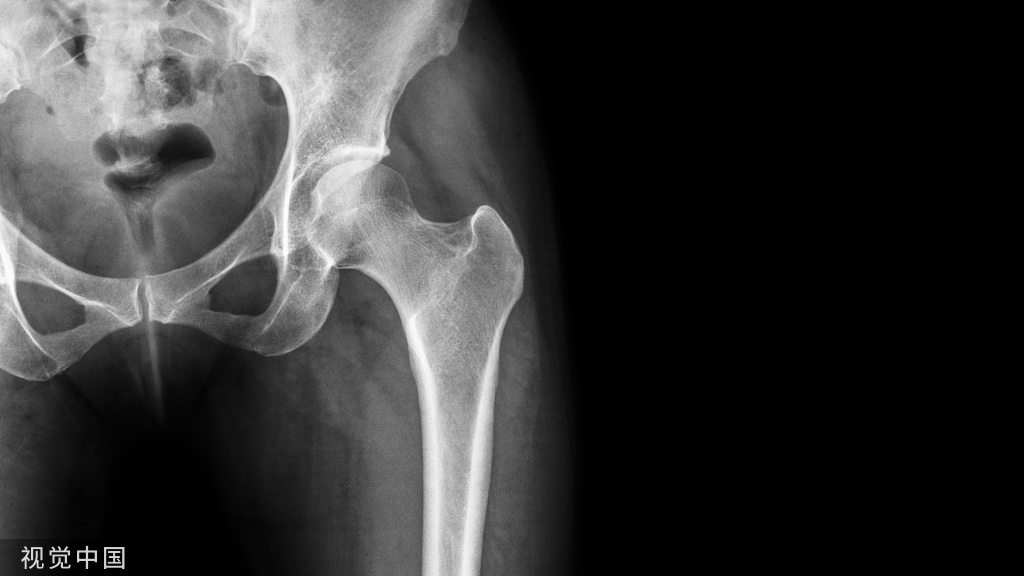

X光片看上去就有点严峻:双侧坏死的面积较大,所幸还没有塌陷。